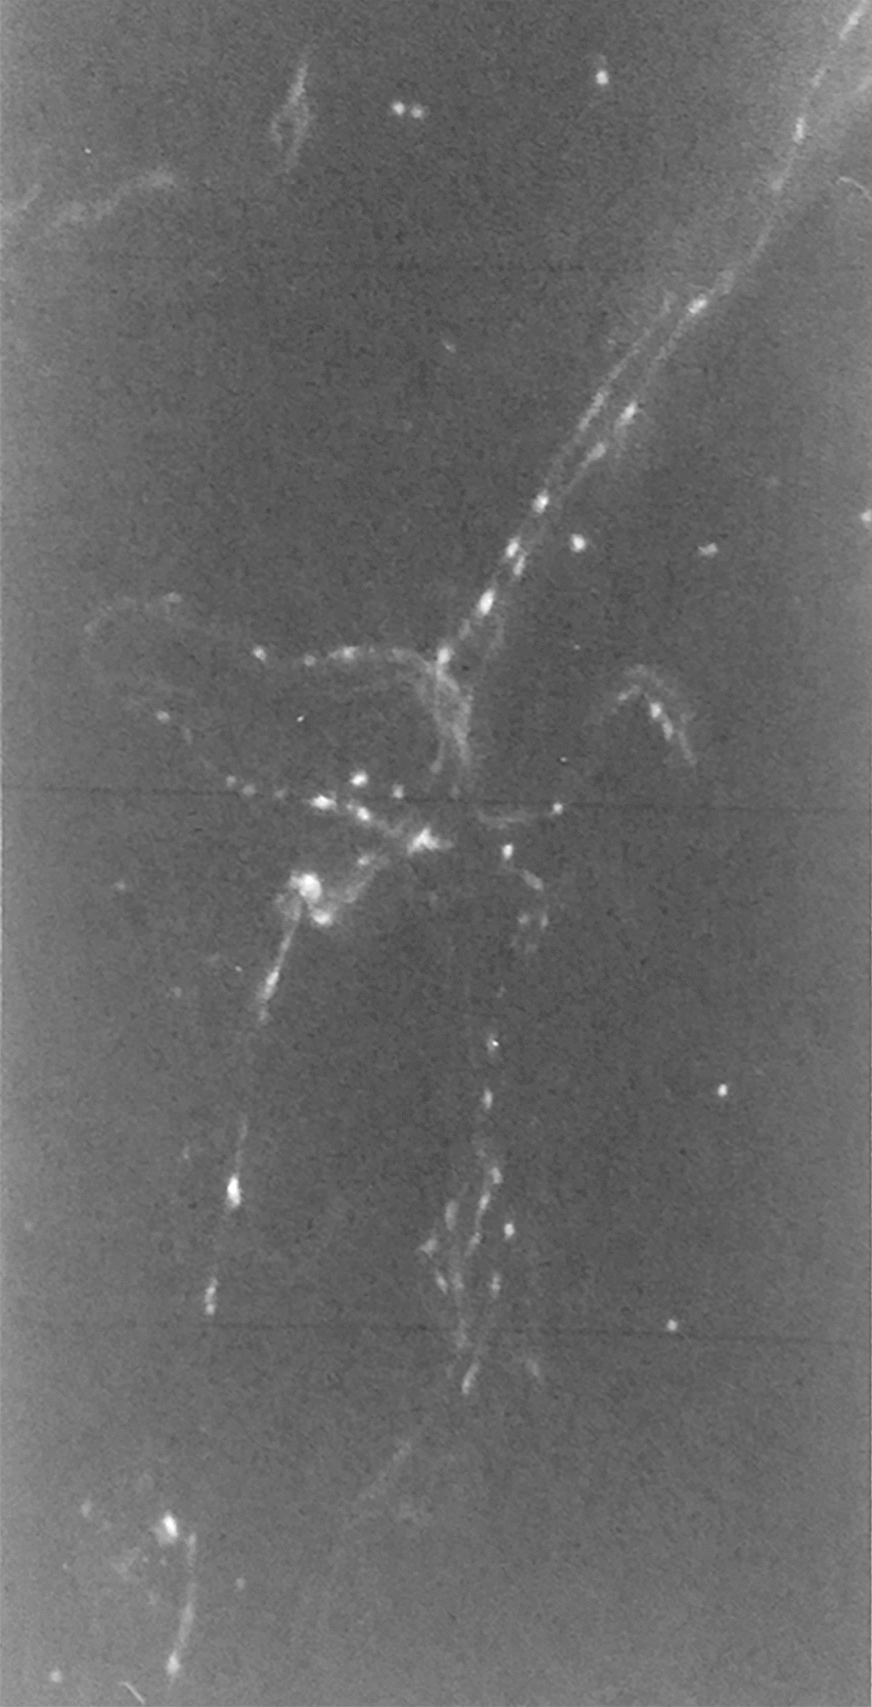

In the preparations regarding the suprachoroidal lamina, we found the ciliary nerves, with a rectilinear course, directed towards the ciliary body. The branches that these nerves yield to the underlying vascular lamina are preserved intact. Among the choroidal branches of posterior short ciliary nerves, there is a certain number of fibers with specific fluorescence for catecholamines. From the ciliary branches, there were numerous collateral bundles consisting of intensely fluorescent fibers whether of tortuous or linear distribution. Only a small part of the fibers originating from ciliary nerves branches appear fluorescent at the level of the suprachoroidal lamina (Fig. 1).

Fig. 1.

Histologic observation of ciliary nerve branches with poor fluorescence at the level of the suprachoroidal lamina (×400)